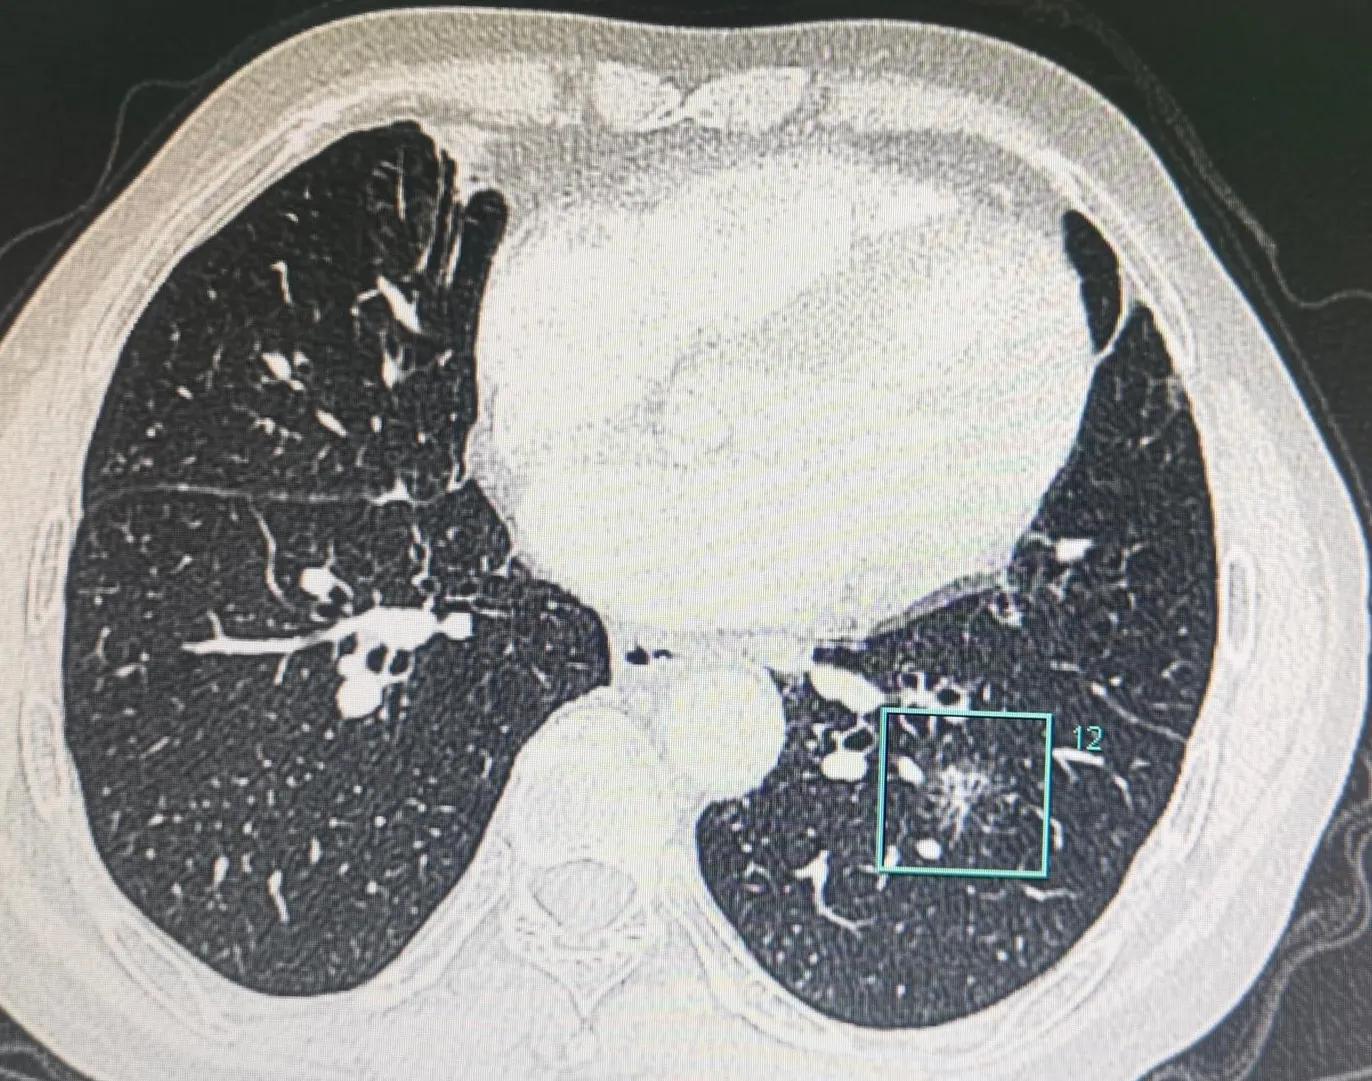

戴主任,您好!我爸爸情况,男,67岁,吸烟多年。2020年11月体检第一次提示结节(体检之前持续咳嗽2个月左右,未做抗炎治疗),大小17*13(2018年7月体检时没有)。2022年5月再次体检时,报大小15*11(后来请医生再次看过应该是测量误差)。之后马上做了增强CT,图片都附在下面。不知道您是否能看得清楚,拜请您百忙之中帮我看看我爸爸这个结节,是不是尽快要手术了?大概是什么性质了呢?手术可以微创吗?(这边胸外科医生说纵隔窗淋巴结稍大,怕影响微创操作)手术的话是要叶切吗?这个年龄预后会怎么样呀?自从复查以来我真的没有一天不焦虑,满脑子都是这个事情。麻烦您了,非常感谢您!也祝您工作顺利,生活愉快!

戴主任,您好!非常抱歉又要来打扰您。前两天发过贴也得到您的回复建议是外科手术干预,我马上挂号看了本地三甲知名胸外科主任医生,他看完电子影像的判断是可以手术,但由于结节位置比较深,纵隔内淋巴细胞压制的比较厉害(我理解是这个意思,可能不是医生的原话),只能进行开放性手术,叶切,且需要动一根肋骨。听到这个话,我焦虑万分,寝食难安,我好不容易说服爸爸同意进行手术,但如果开放性的他肯定不会同意,再加上他今年67岁了,我怕开放性手术一是风险太大,二是恢复起来太难,所以恳请您能看一下电子影像(我拷贝了增强CT的电子影像),然后帮我判定一下是否可以进行微创手术?如果您说可以,我就带他来找您面诊和手术。再次恳求您能帮我看看电子影像,分析一下手术形式,万分感谢您!

有了戴主任的定性,我马上开始联系医院,在朋友的推荐和帮助下,决定在当地一家医院做手术,并也成功说服了爸爸做好心理准备接受手术。但在看门诊时,主任医生告诉我说他看了增强CT的影像,由于我爸爸的肺部有粘黏和钙化淋巴结的影响,大概率只能做开放性的手术(也就是常说的开胸),我爸一听就表示了拒绝,怎么都不同意,我也一下子脑瓜子嗡嗡的,当机的感觉,无法思考…

非常幸运的我们,终于在5月30日,来到了戴主任面前,我当时真挺紧张的,以至于有些问题都忘记了。戴主任微笑着,声音非常好听,非常温和且非常有力量,他仔细看了ct之后,说手术吧,90%微创没问题,说着就给我们开了住院单。